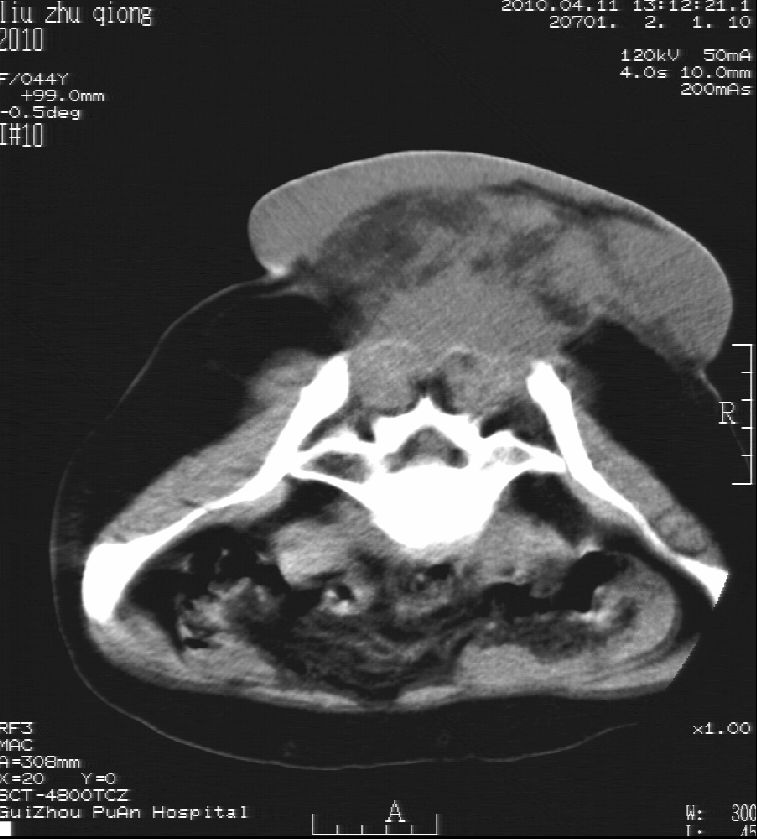

刘某,女,44岁,生第一胎时发现腰背部肿块,黄豆大小,至今17年,呈逐年增大,现行ct检查如下,敬请各位指点。

病史:女,44岁,腰背部肿块,黄豆大小,17年,呈逐年增大。

ct示:骶骨见软组织密度影,似见细条状,或花边状高密度影,考虑不典型钙化灶,向后生长,超出皮肤,可见骶骨破坏,第5幅ct图似与骶管相通。

诊断:脊索瘤

病程长,生长慢,肿块巨大,考虑神经纤维瘤,脂肪密度可以用肿瘤生长过程中包裹入皮下脂肪解释。